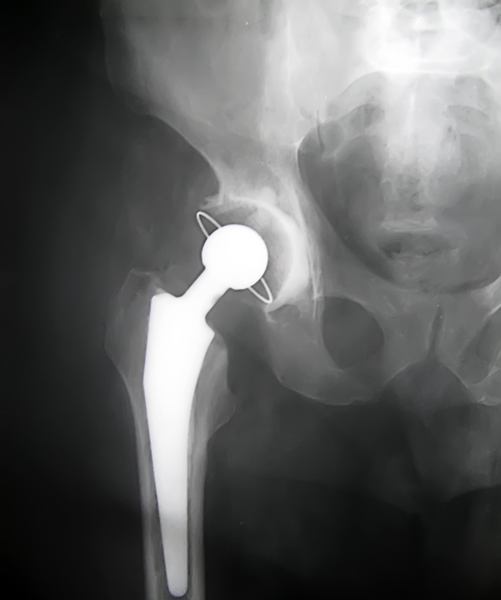

can you tell if its 9 days or 9months? then i can give Some advice. do you have any other xrays?show them as well

Xray you sent me shows total hip replacement, if she still got pain then better to contact the surgeon who has operated to rule out infection or other technical problems which he probably faced during surgery. However You are welcome to see me in Islamabad.

From the Xray it appears the implant has loosened.